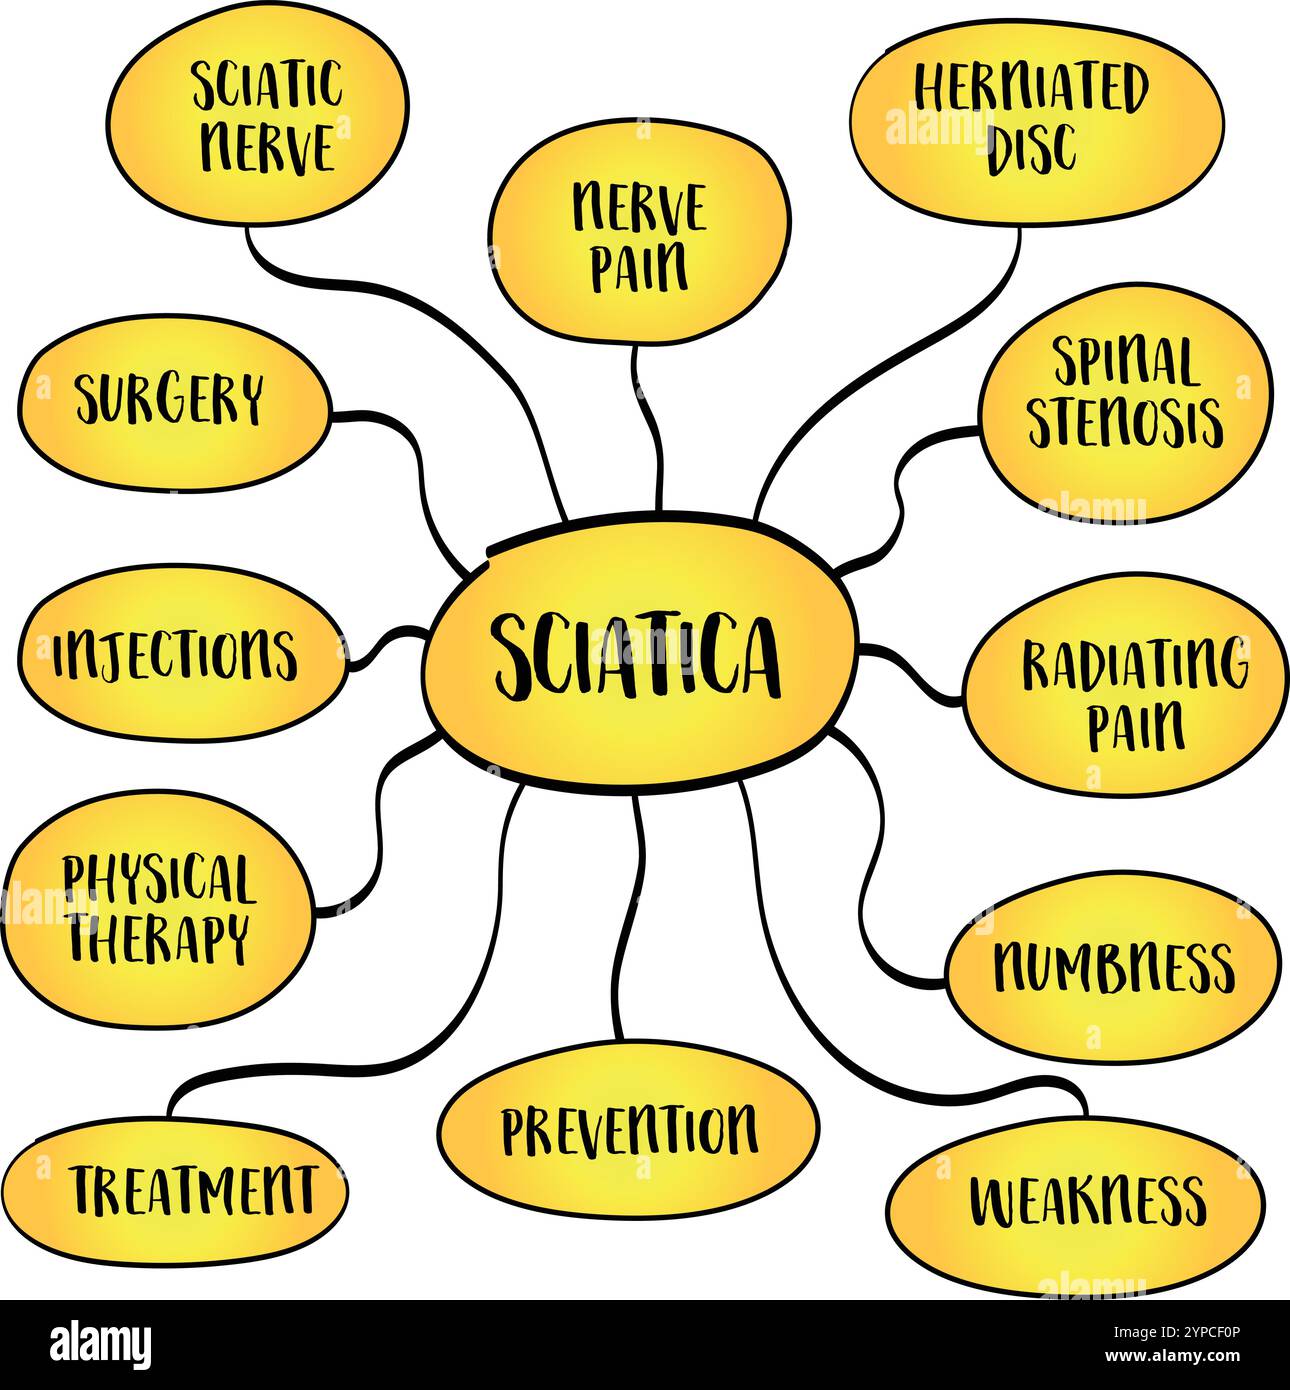

Sciatique se réfère à la douleur qui rayonne le long du chemin du nerf sciatique, le plus grand nerf dans le corps, infographie de carte mentale. Banque D'Imageshttps://www.alamyimages.fr/image-license-details/?v=1https://www.alamyimages.fr/sciatique-se-refere-a-la-douleur-qui-rayonne-le-long-du-chemin-du-nerf-sciatique-le-plus-grand-nerf-dans-le-corps-infographie-de-carte-mentale-image625456387.html

Sciatique se réfère à la douleur qui rayonne le long du chemin du nerf sciatique, le plus grand nerf dans le corps, infographie de carte mentale. Banque D'Imageshttps://www.alamyimages.fr/image-license-details/?v=1https://www.alamyimages.fr/sciatique-se-refere-a-la-douleur-qui-rayonne-le-long-du-chemin-du-nerf-sciatique-le-plus-grand-nerf-dans-le-corps-infographie-de-carte-mentale-image625456387.htmlRF2Y9G003–Sciatique se réfère à la douleur qui rayonne le long du chemin du nerf sciatique, le plus grand nerf dans le corps, infographie de carte mentale.

Sciatique se réfère à la douleur qui rayonne le long du chemin du nerf sciatique, le plus grand nerf dans le corps, infographie vectorielle de carte mentale. Illustration de Vecteurhttps://www.alamyimages.fr/image-license-details/?v=1https://www.alamyimages.fr/sciatique-se-refere-a-la-douleur-qui-rayonne-le-long-du-chemin-du-nerf-sciatique-le-plus-grand-nerf-dans-le-corps-infographie-vectorielle-de-carte-mentale-image633370886.html

Sciatique se réfère à la douleur qui rayonne le long du chemin du nerf sciatique, le plus grand nerf dans le corps, infographie vectorielle de carte mentale. Illustration de Vecteurhttps://www.alamyimages.fr/image-license-details/?v=1https://www.alamyimages.fr/sciatique-se-refere-a-la-douleur-qui-rayonne-le-long-du-chemin-du-nerf-sciatique-le-plus-grand-nerf-dans-le-corps-infographie-vectorielle-de-carte-mentale-image633370886.htmlRF2YPCF0P–Sciatique se réfère à la douleur qui rayonne le long du chemin du nerf sciatique, le plus grand nerf dans le corps, infographie vectorielle de carte mentale.

Sciatique se réfère à la douleur qui rayonne le long du chemin du nerf sciatique, le plus grand nerf dans le corps, infographie de carte mentale. Banque D'Imageshttps://www.alamyimages.fr/image-license-details/?v=1https://www.alamyimages.fr/sciatique-se-refere-a-la-douleur-qui-rayonne-le-long-du-chemin-du-nerf-sciatique-le-plus-grand-nerf-dans-le-corps-infographie-de-carte-mentale-image624275730.html

Sciatique se réfère à la douleur qui rayonne le long du chemin du nerf sciatique, le plus grand nerf dans le corps, infographie de carte mentale. Banque D'Imageshttps://www.alamyimages.fr/image-license-details/?v=1https://www.alamyimages.fr/sciatique-se-refere-a-la-douleur-qui-rayonne-le-long-du-chemin-du-nerf-sciatique-le-plus-grand-nerf-dans-le-corps-infographie-de-carte-mentale-image624275730.htmlRF2Y7J61P–Sciatique se réfère à la douleur qui rayonne le long du chemin du nerf sciatique, le plus grand nerf dans le corps, infographie de carte mentale.